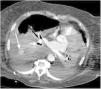

A 75-year-old woman and ex-smoker was admitted to the ICU due to respiratory failure secondary to pneumonia. The clinical course proved torpid, with the development of acute respiratory distress syndrome and the need for prolonged mechanical ventilation. Weaning was complicated by the appearance of bilateral pleural effusion, requiring the ultrasound-guided placement of a pleural drain (Pleurocath® 12 French). After 30 min, the patient developed severe hypotension, perspiration and paleness. Following initial stabilization, a chest CT scan was requested, evidencing right hemothorax and a rounded image suggestive of a pseudoaneurysm of the peripheral pulmonary circulation (Fig. 1). After consulting Interventional Radiology, the decision was made to perform pulmonary angiography, which confirmed the existence of an arterial pseudoaneurysm arising from a branch of the right descending lobar artery (Fig. 2). Coil embolization was performed (Fig. 3), followed by a good course, and the patient was discharged to the ward without complications.